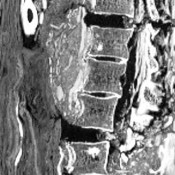

Μέλος της ερευνητικής ομάδας που μελετούσε τη μούμια στην Πορτογαλία τα δύο προηγούμενα έτη, ανακοίνωσε την Κυριακή ότι πρόκειται για τη δεύτερη αρχαιότερη περίπτωση καρκίνου του προστάτη που γνωρίζουμε. Η μούμια ανήκει σε άνδρα που πέθανε γύρω στα 40 του χρόνια. Οι ερευνητές «πέρασαν» τη μούμια από αξονικό τομογράφο. Η εξέταση έδειξε μικροτραυματισμούς στη σπονδυλική στήλη και στην περιοχή της λεκάνης, οι οποίοι παραπέμπουν σε μεταστάσεις.